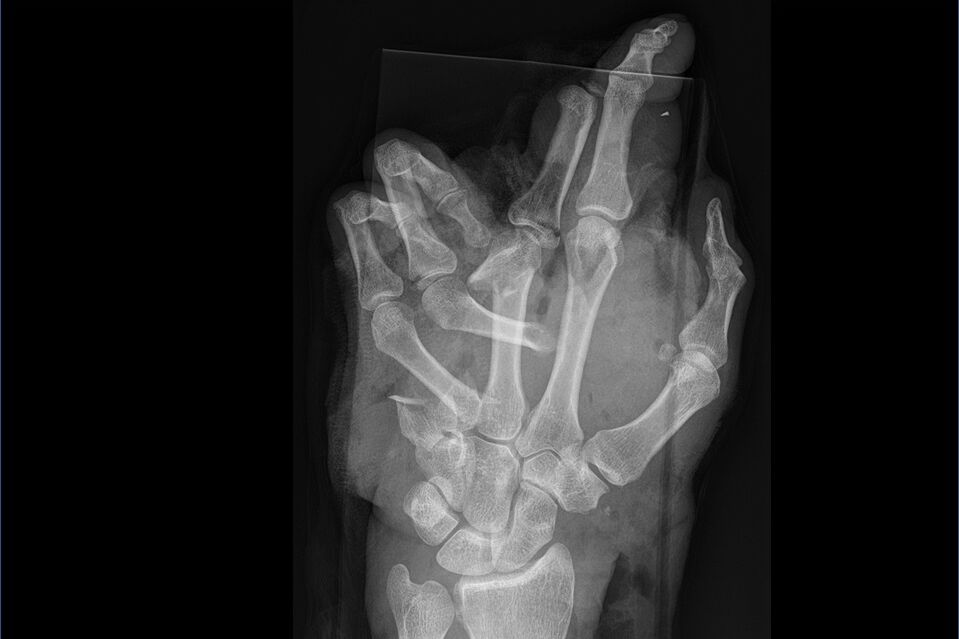

Chronik/Wien NEWSBöller in Hand explodiert: Bub (11) sprengte sich Finger weg by AUSZTRAJOB NEWSDecember 7, 20250 Share0 Der 11-Jährige hatte in einem Park in Wien-Simmering einen Böller gezündet, der plötzlich explodierte. Eine Passantin rief die Rettung.